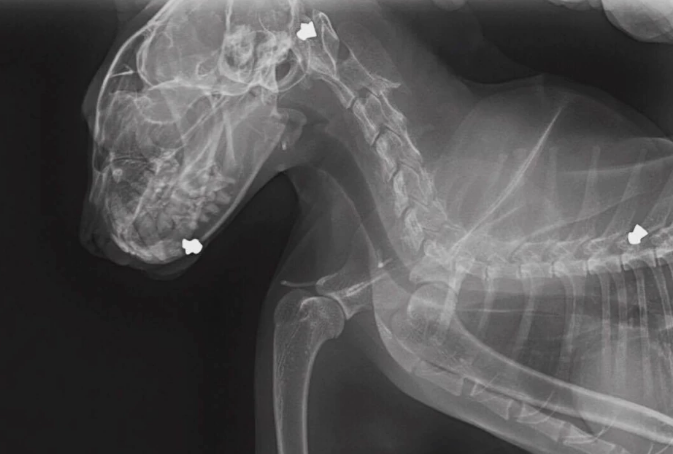

Il avait des plombs dans la tête, les joues, le cou, sa mâchoire, son dos. Le vétérinaire a dit qu'à voir la manière dont les plombs s'étaient logés dans sa tête, c'est comme si la carabine à plomb avait été tenue braquée sur sa tête et son corps... On a fait ça volontairement.

Fort heureusement, Biggie s'en est sorti par miracle. Ironie de l'histoire, le chat a été prénommé ainsi pour rendre homme au rappeur Notorious Big, abattu par balles en 1997. Nicole, quant à elle, ne comprend pas cet acte de cruauté, et craint que le coupable ne se trouve parmi ses voisins. La SPCA, de son côté, mène l'enquête pour tenter de retrouver le ou les responsables.